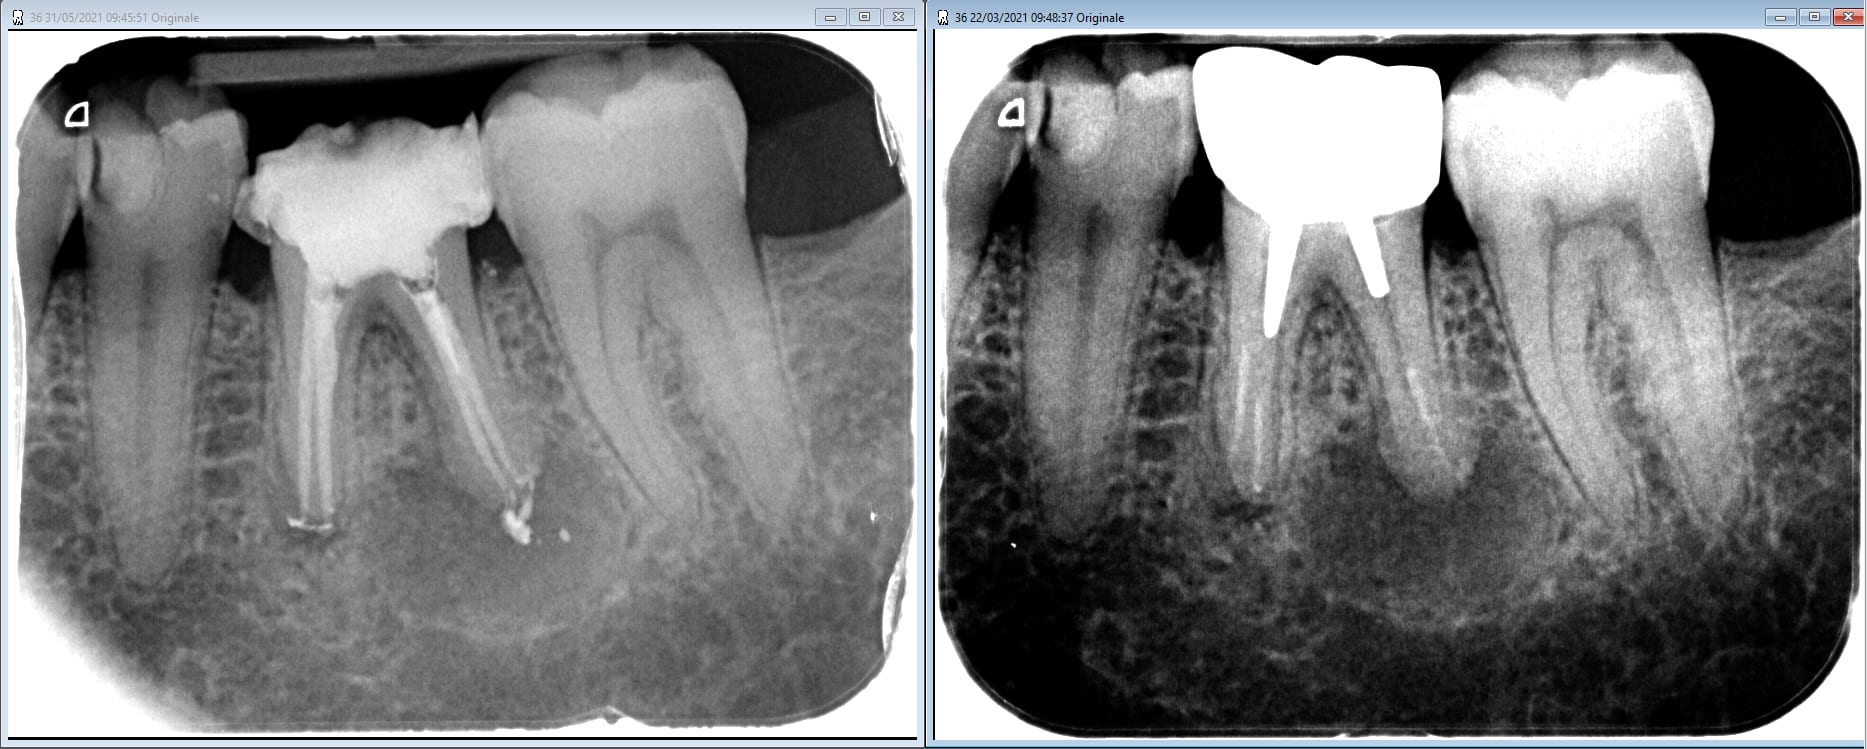

Non mais là c'est tricherie avec tes 2 dents infectées . Sur que la salive était plus saine que le contenu des canaux . Alors pas de prison , mais juste un mois qu'avec des cmu ou mgen au choix , et tu prends aussi tous les dets d'enlaye ;o)

RIP pour la latérale ou pas !!!!